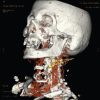

Intra-parenchymal sialolithiasis and subsequent fibrosis of the submandibular salivary glands is a rare disorder. The resulting swelling, pain, and infection derives affected patients to seek treatment. We present the case of an 85-years-old Saudi male patient who suffered from repeated swelling and infection in the left submandibular region which was misdiagnosed and treated for over 60 years as dental infection, infected skin sebaceous gland or lipoma. The presented case represents the largest intra-glandular submandibular stone with the longest duration ever reported in the medical literature.